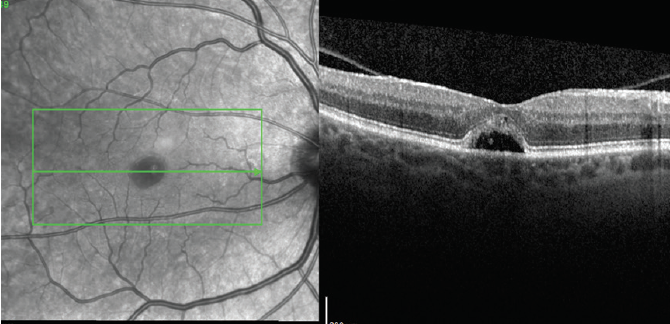

Figure 3. High-density OCT scan through the fovea 6 weeks after starting NSAID treatment showing a closed MH with subfoveal fluid pocket.

The patient was prescribed ketorolac eye drops 0.5% three times a day OD. After 6 weeks, the MH closed and a small pocket of subfoveal fluid persisted, but no macular edema was noted. The patient’s visual acuity and symptoms had not changed (Figure 3).